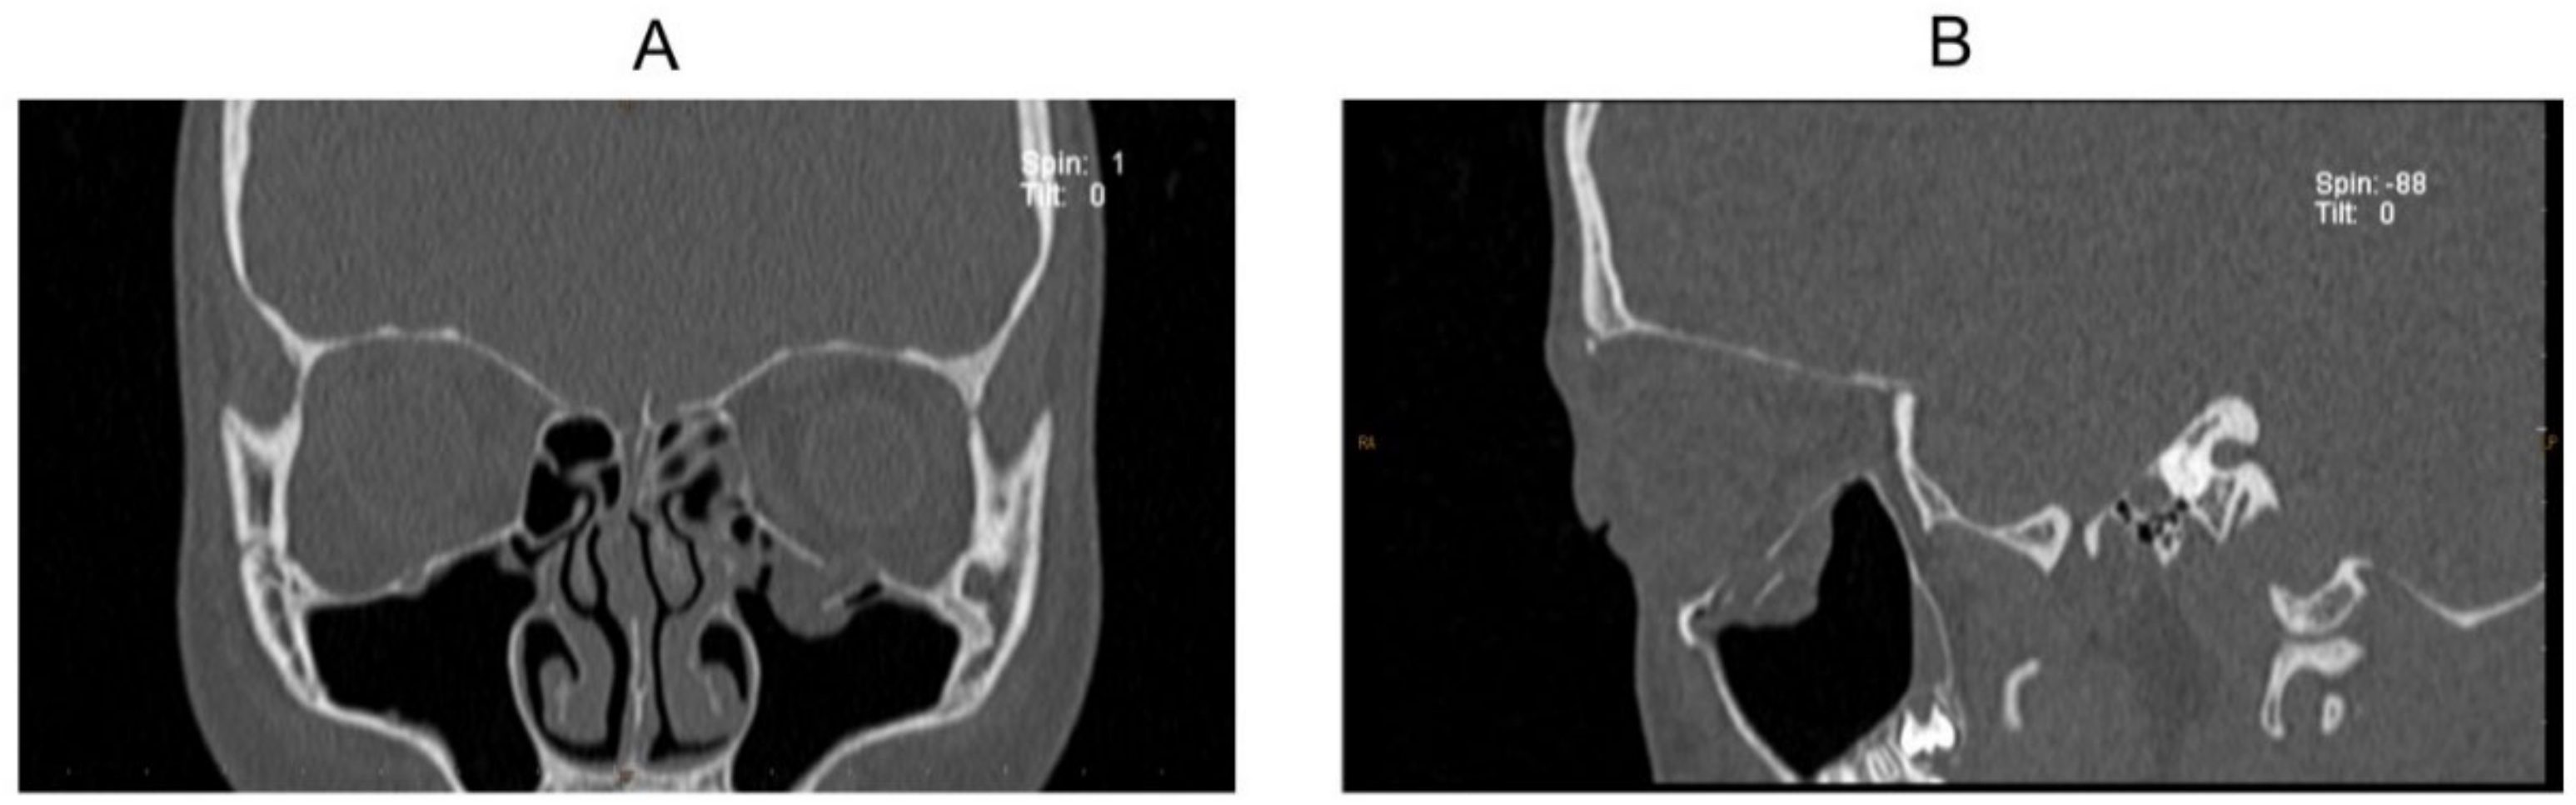

Case 9

Case 10